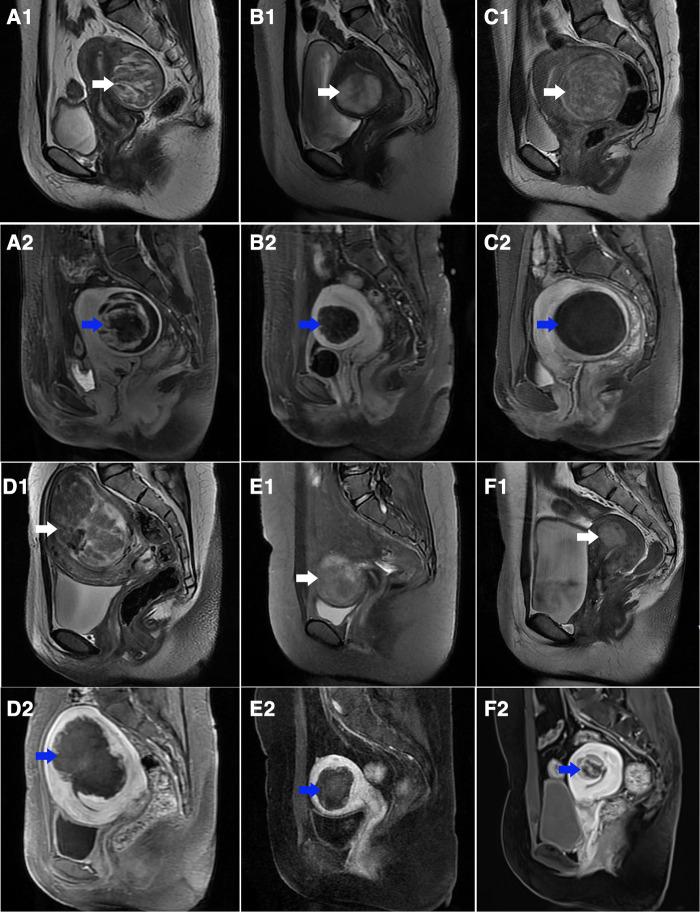

339 women with 368 hyperintense uterine fibroids on T2WI who underwent single-session HIFU ablation were enrolled, including 283 patients with 303 fibroids in the single-session HIFU (sHIFU) group and 56 patients with 65 fibroids in the HIFU pretreated with GnRH-a (Gn-HIFU) group. The signal intensity (SI) value and standard deviation (SD) value were measured based on T2WI, and the fibroids were further subdivided into heterogeneous hyperintense fibroids, slightly homogeneous hyperintense fibroids and markedly homogeneous hyperintense fibroids as 3 subgroups (HHF, sHHF and mHHF group respectively). Treatment time, sonication time, dose, non-perfused volume (NPV), NPV per sonication time, non-perfused volume ratio (NPVR), energy effect ratio (EEF) and adverse events were recorded.

纳入339例接受单次HIFU消融的T2WI上有368个高信号子宫肌瘤的女性,其中单次HIFU(sHIFU)组283例患者有303个肌瘤,GnRH-a预处理的HIFU(Gn-HIFU)组56例患者有65个肌瘤。基于T2WI测量信号强度(SI)值和标准差(SD)值,并将肌瘤进一步细分为异质性高信号肌瘤、轻度均匀性高信号肌瘤和显著均匀性高信号肌瘤作为3个亚组(分别为HHF、sHHF和mHHF组)。记录治疗时间、超声照射时间、剂量、无灌注体积(NPV)、每超声照射时间的NPV、无灌注体积比(NPVR)、能量效应比(EEF)和不良事件。